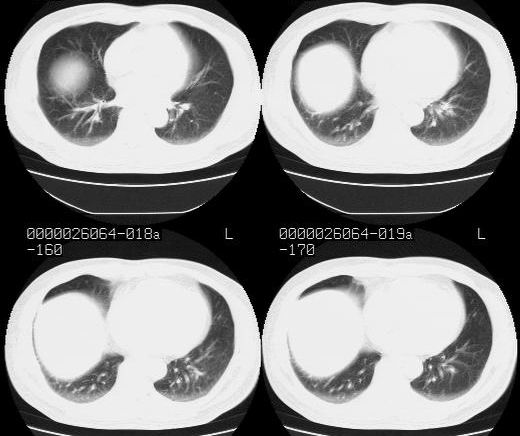

标题: CT15869:男性,71岁,因咳嗽而就诊,请讨论右上肺病变性质 [打印本页]

标题: CT15869:男性,71岁,因咳嗽而就诊,请讨论右上肺病变性质

患者,男性,71岁,因咳嗽而就诊,

典型的右肺中心性肺癌并纵隔淋巴结转移

右肺中心性肺癌并纵隔淋巴结转移可能性大!

考虑右肺中心性肺癌并右肺门及纵隔淋巴结转移。

1,右肺中心型ca,气管隆突旁淋巴结转移。

2,右膈明显抬高,建议肝脏扫描排除转移或原发灶。